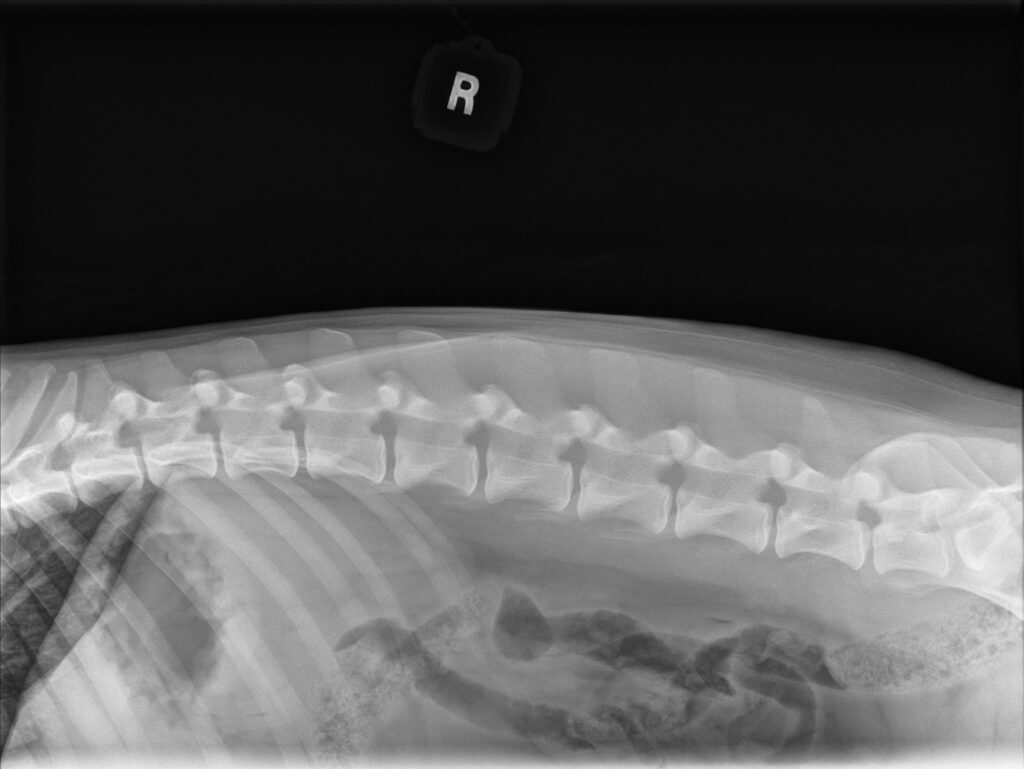

Spine: LTV0